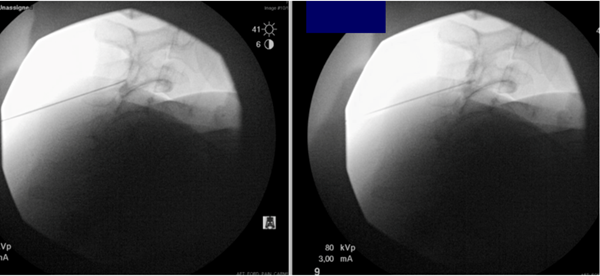

The medial branch block was carried out using fluoroscopic guidance. Gadobutrol was injected at the left C3, C4, and C5 medial branch targets. No vascular uptake was visualized on fluoroscopic examination. The procedure was completed without any immediate complications. Post-procedurally, the patient was observed and noted to be alert, oriented, and conversant. She was cleared for discharge after standing and verbalizing her discharge instructions appropriately.

Figure 1: Left cervical medial branch block under fluoroscopic guidance using GBCAs